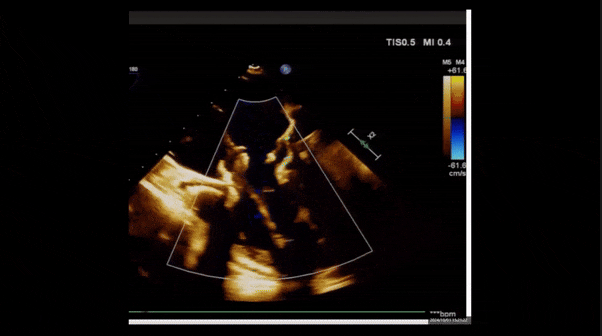

2、彩色多普勒顯示:收縮期三尖瓣口返流束起源于后隔交界、前后葉之間及前隔交界,返流束縮流頸最大寬度27mm,三尖瓣返流口EOA=2.02cm2,返流容積124ml,收縮期三尖瓣返流峰值速度2.64m/s,返流峰值壓差28mmHg,PAPs 43mmHg,舒張期三尖瓣口平均跨瓣壓差1mmHg,肝左靜脈可見明顯逆向血流波。

術中經食道超聲輔助下可見LuX-Valve Plus夾持件抓捕瓣葉狀態良好,夾持件在位,室間隔錨定位置良好,假體瓣膜整體錨定狀態穩固。

術后即刻經食道超聲可見,三尖瓣假體瓣膜位置合適,牛心包瓣葉運動狀態良好,開閉正常,瓣周及瓣葉對合緣處未見明顯返流,心電圖及心包狀態較術前無明顯變化。